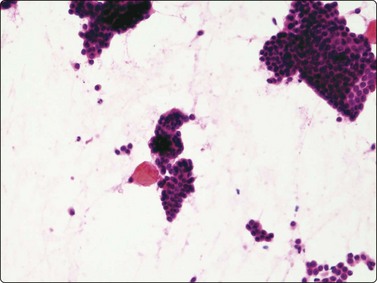

Phyllodes tumor (Figs 7.29-7.32)117-123

Phyllodes tumor (PT) is a biphasic epithelial/stromal neoplasm of the breast. In contrast to fibroadenoma, PT is a rare tumor comprising less than 0.3% of all breast tumors. It is classified as benign, low grade (borderline) and high grade (malignant) based on histologic features. Stromal cellularity and overgrowth, atypia, mitotic activity, and invasive growth pattern at tumor periphery define whether a PT is benign, low grade or high grade. Benign PTs do not metastasize, but may locally recur if incompletely excised. High-grade PTs behave like sarcomas with higher potential for recurrence and metastasis. Low-grade PTs fall in between.

image image

Fig. 7.29 Benign phyllodes tumor

(A) Huge, slowly growing breast mass in a 40-year-old woman; (B) FNB smears were cellular, dominated by dispersed cells with bare oval or plump spindle nuclei (MGG, HP).

Fig. 7.30 Borderline phyllodes tumor

Smears dominated by mildly atypical, both plump and slender spindle cells, single and in loose tissue fragments with fibrous stroma; a few sheets of bland duct epithelium (A, MGG; B, Pap, HP).

Fig. 7.31 Malignant phyllodes tumor

(A) Mainly dispersed spindle cells showing moderate nuclear atypia, no epithelial cells. Invasive growth demonstrated in tissue sections; multiple recurrences (MGG, IP); (B) Another case showing numerous spindle cells with more marked atypia and a sheet of bland epithelium (Pap, HP).

image

Fig. 7.32 Fibroadenoma mimicking benign phyllodes tumor on core needle biopsy (H&E, IP).

Aspiration biopsy can accurately diagnose malignant PTs in most cases. On the benign/borderline end of the spectrum, cytologic features of fibroadenoma and PT overlap, making FNA diagnosis difficult (see Fig. 7.23). Precise preoperative distinction is important for optimal patient management. Classic cytologic features in PT are similar to fibroadenoma. However, as opposed to fibroadenoma, stromal fragments are larger, increased in number (stromal overgrowth) and are hypercellular (phyllodes fragments); the single stromal cells in the background are plumper than the typical oval bare nuclei seen in fibroadenoma. These single cells are intact spindled cells with retained cytoplasm (not naked nuclei), and variable degrees of nuclear atypia with nucleoli and pleomorphism. However, some of these features may be entirely lacking in benign and low-grade PTs even after retrospective review of smears, making their differentiation from fibroadenoma virtually impossible. It is not surprising that a considerable portion of benign and low-grade PTs are initially diagnosed as fibroadenoma on cytology.117,120,121 This in part reflects sampling problems as hypo- and hypercellular areas tend to alternate within PTs. Another important diagnostic pitfall in PTs is the presence of significant epithelial proliferation including atypical ductal epithelial hyperplasia. If these areas are sampled by aspiration biopsy, this may lead to a false diagnosis of epithelial neoplasm. In our experience, we encountered this problem even with high-grade (malignant) PTs; one such retroareaolar case required core biopsy due to inability of aspiration biopsy to rule out an atypical papillary lesion. In addition, focal malignant transformation may be missed by FNA sampling.

Page 174

The diagnosis of PT on CNB is equally as challenging (Fig. 7.32). It is especially difficult to differentiate cellular fibroadenoma from benign/low-grade PT. In comparison, in one study, the possibility of PT was raised in 23% on FNB and 65% on core biopsy.122 In two others, 11 of 44 (25%), and 9 of 23 (39%) of surgically resected PTs were reported as fibroadenoma or benign on core biopsy.123,124 Similar to FNB, some PTs are diagnosed as fibroadenoma on core biopsy because of tumor heterogeneity. Marked nuclear pleomorphism and mitotic activity suggest frankly malignant phyllodes tumor (Fig. 7.31A,B).